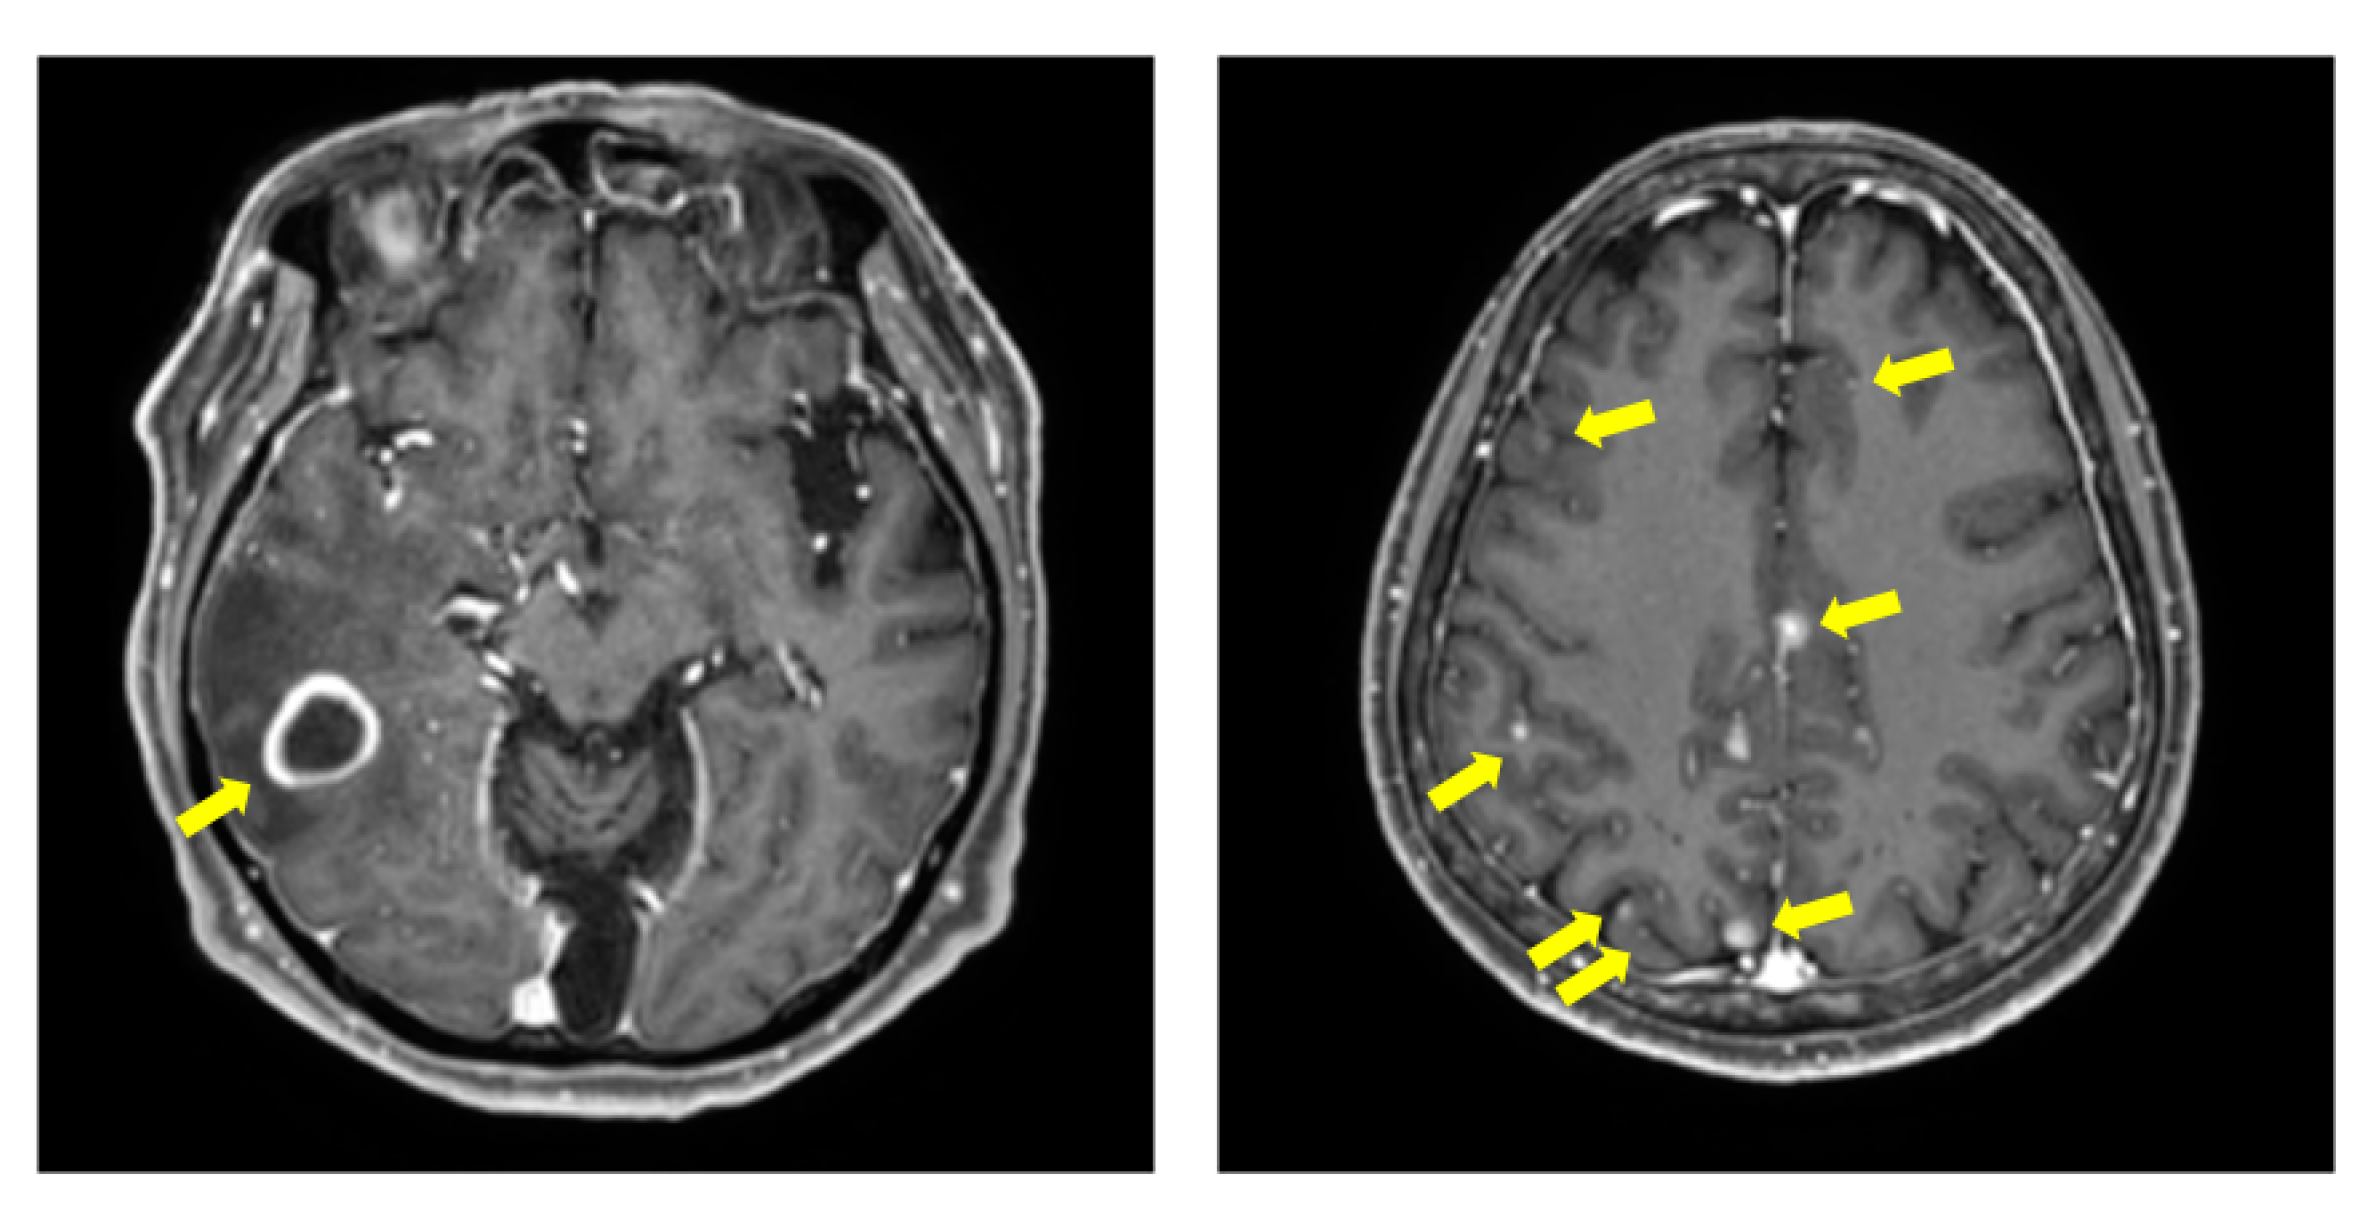

However, these studies have dealt with BM with relatively large volumes, and few studies have described [12], detected, and segmented BM with small volume that pose a challenge to physicians in clinical practice. The cases of large-volume BM and small-volume BM are showed in Figure 1.

Figure 1. Examples of T1Gd images with BM. The (left) image shows the randomly selected samples of large-volume BM. The (right) image shows the randomly selected samples of small-volume BM with multiple metastases. In each images, yellow arrows indicate the BM.